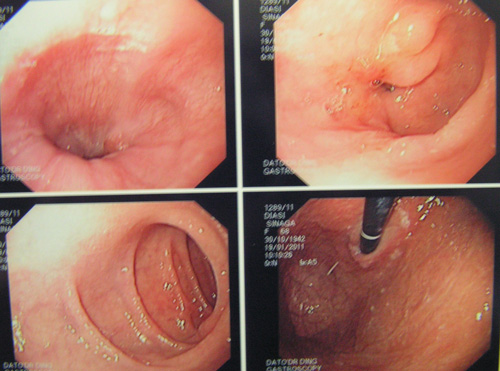

Tidak puas, PC lalu pergi ke sebuah rumah sakit swasta di Ipoh. Pada pemeriksaan X – ray didada kirinya menunjukkan adanya efusi pleura (yaitu adanya cairan di paru-paru kirinya). Cairannya disedot keluar. Sebuah ultrasonagraphy ( dibagian perut ) pada tanggal 23 September 2009 menunjukkan sebuah lesi berukuran 2,6 cm ( diperkirakan hepatoma atau kanker hati) di lobus sebelah kanan. Selain itu, pada organ hatinya sudah terjadi sirosis hati ( mengeras ) dengan hipertensi portal dan adanya ascites ( adanya cairan dibagian perut ). Organ Limpa nya membesar.

Biopsi dari lesi tersebut tidak dapat dilakukan mengingat telah terjadinya ascites, trombosit yang rendah dan keberadaan tumor yang terlalu dalam dan berdekatan dengan vena portal.